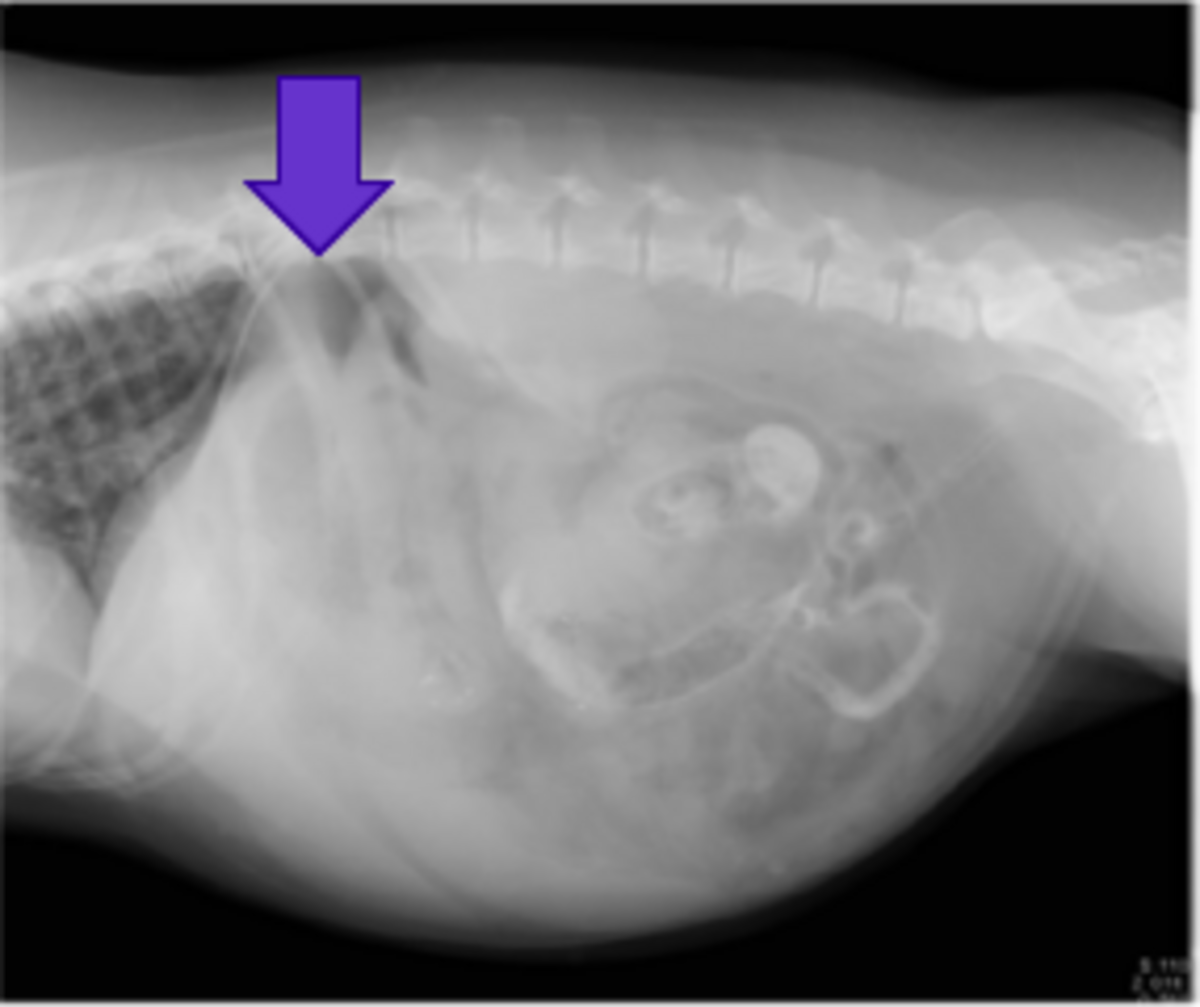

雑種猫、1歳、避妊雌、体重3.6 kg(BCS:3/5)です。3カ月前に突然、発熱と元気および食欲低下が認められたため、近医にて抗菌薬投与(セフォベシンナトリウム)、静脈輸液等で治療を行ったところ、状態が改善しました。その後、再び元気がなくなったため、抗菌薬投与を行うも回復せず、腹水貯留が確認されたため精査を希望して本学獣医臨床センターを紹介受診されました。初診時の身体検査では腹囲膨満が確認され、血液検査では、重度な好中球数の増加(表5)、低アルブミン血症(1.5g/dL)が確認されました。X線検査では、腹腔内の不透過性亢進が認められました(図7)。

図7:腹部レントゲン